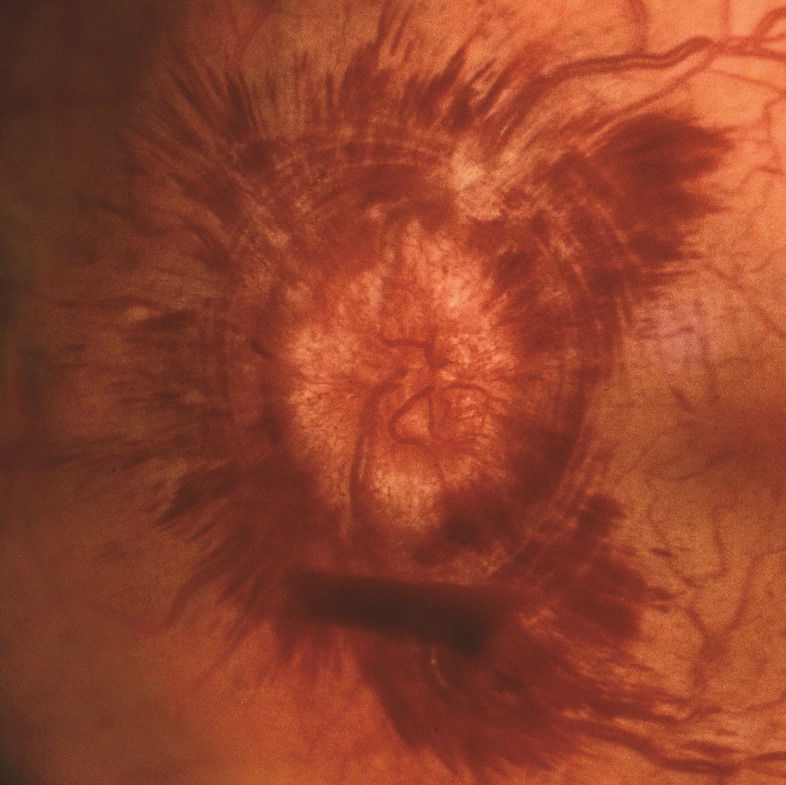

Severe optic disc edema. Massive optic disc edema is present in this patient with intracranial hypertension and systemic hypertension. The optic nerve is elevated and enlarged. Hemorrhage is present in the nerve fiber layer (flame-shaped hemorrhages) and within the retina (dot/blot hemorrhages). The swollen nerve elevates and laterally displaces the choroid and retina, creating concentric chorioretinal folds called Paton lines.

Source: Martin TJ, Corbett JJ. Practical Neuroophthalmology; 2013.